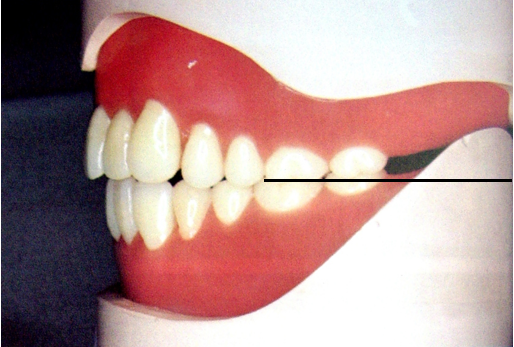

磨牙后垫的形态和位置比较稳定,作为排人工牙时的解剖标志;垂直向:下颌第一磨牙的颌平面与磨牙后垫的1/2处等高;

前后向:下颌第二磨牙应位于磨牙后垫前缘;

颊舌向:磨牙后垫颊面、舌面向前与下颌尖牙的近中面形成一个三角形。